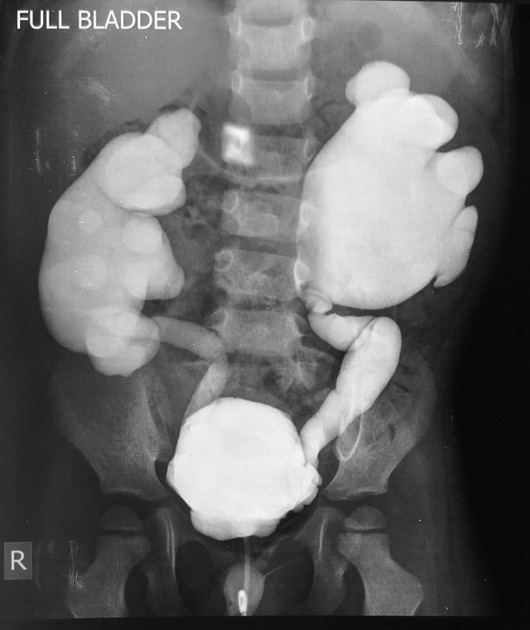

Микционная цистоуретрография служит основным методом выявления ПМР, особенно при гидронефрозе. Позволяет определять степень тяжести процесса [1].

Радиоизотопная цистография используется для послеоперационного контроля ПМР, но не детализирует степень рефлюкса и анатомические аномалии [1].